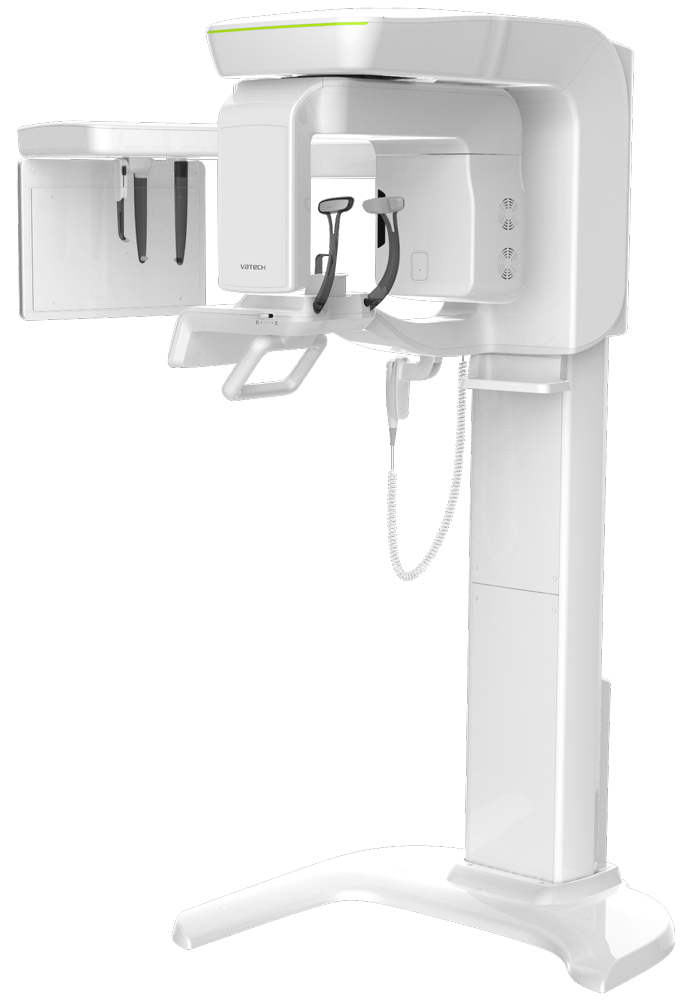

Smart Plus

PANO/CEPH/CBCT

Qualità dell’immagine

5×5 potenziata

Una scansione, due immagini

FOV anatomico 12×9

Tecnologia Compressed Sensing

Scansione 3D

per modelli

Valore diagnostico professionale

con immagini cefalometriche

Una scansione, due immagini

Con una sola scansione, Smart Plus consente di ottenere non solo un’immagine TC, ma anche un’immagine Auto Pano. Questo significa che i pazienti che necessitano di entrambe le immagini non devono sottoporsi a due esami radiografici separati. Inoltre, le immagini TC e Auto Pano vengono visualizzate all’interno di un unico viewer, semplificando la consultazione e migliorando il flusso di lavoro.

FOV anatomico 12×9

L’innovativo FOV di Smart Plus offre un volume con forma ad arcata, che consente una visualizzazione più ampia della dentizione rispetto ad altri dispositivi con lo stesso FOV. Il volume ad arcata permette di visualizzare anche le aree dentali normalmente nascoste.

Compressed Sensing Technology

Vatech migliora in modo significativo la qualità dell’immagine, riducendo drasticamente artefatti e rumore grazie alla Compressed Sensing Technology (CST). Attraverso un processo di ricostruzione iterativa eseguito fino a 10 volte in più rispetto agli standard tradizionali, il sistema riesce a rappresentare l’oggetto in modo più fedele e accurato. La modalità di scansione cefalometrica offre due formati di immagine, LAT e FULL LAT, selezionabili in base alle specifiche esigenze diagnostiche.